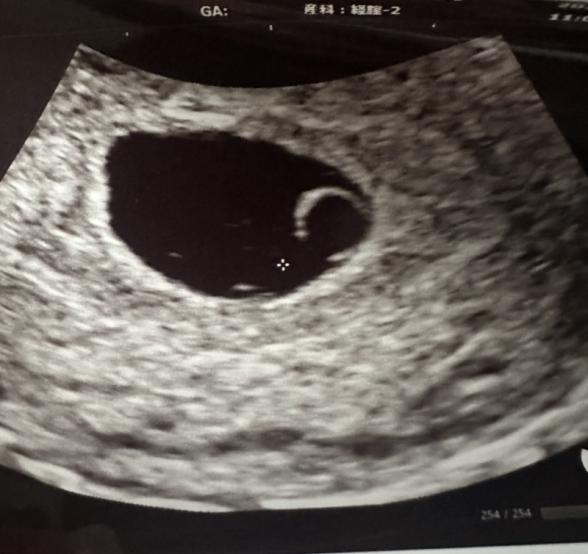

現在7週目。病院は4週目から受診しています。

胎嚢卵黄嚢は確認できておりますが、

1週間程続いており量も少しずつ段々と増えてきていて痛みはないのですが、昨日検診で先生に伝えると6週目頃(15mm)と大きさも変わっていない心拍確認できず稽留流産の可能性があると言われました。

(エコー写真7週目)(2枚目はトイレに付いていた茶色いカスみたいなものです)

エコー写真からですと、稽留流産の可能性がどの程度あるのかはハッキリとは明言できませんが、稽留流産かどうかは、すぐに診断されるわけではなく、まずは経過を見ていくことがほとんどと思います。経過を見ていく中で、心拍が確認できない、大きさが変わらないなどが週数にわたって見られるようであれば、時期を見て判断されると思いますよ。出血もあり、ママさんとしてはご心配になりますよね。お腹の痛みや出血量が増えるなどがないかなども併せて見ていただくといいと思いますよ。今はご心配なお気持ちがあると思いますが、今の週数ですと、特にできることがないので、まずはご無理なさらずお過ごしいただいて、赤ちゃんの生きる力を信じてあげてくださいね。